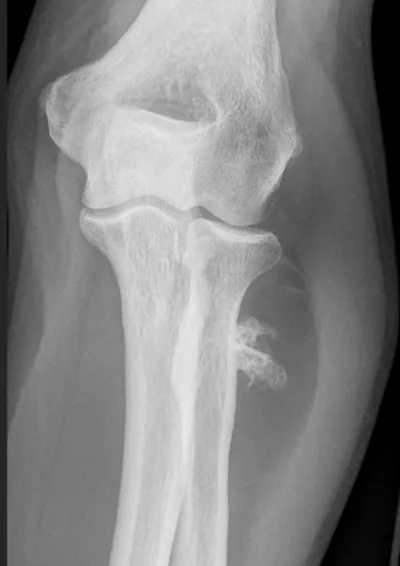

- This collection contains 4 radiology images related to forearm, including various imaging modalities such as X-rays, MRIs, CT scans, and ultrasound images commonly used in medical diagnosis and education.